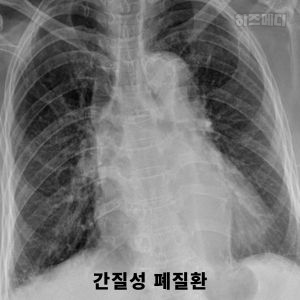

2) 간질성 폐질환

간질성 폐질환은 폐에 염증이 생기거나, 폐 조직이 딱딱해지는 질병입니다. 이렇게 되면 폐가 제대로 부풀어 오르지 못하고, 공기가 잘 들어가지 않게 됩니다. 이 병은 주로 이유 없이 생기기도 하고, 특정 약물이나 독성 물질에 노출된 후에 발생할 수 있습니다.